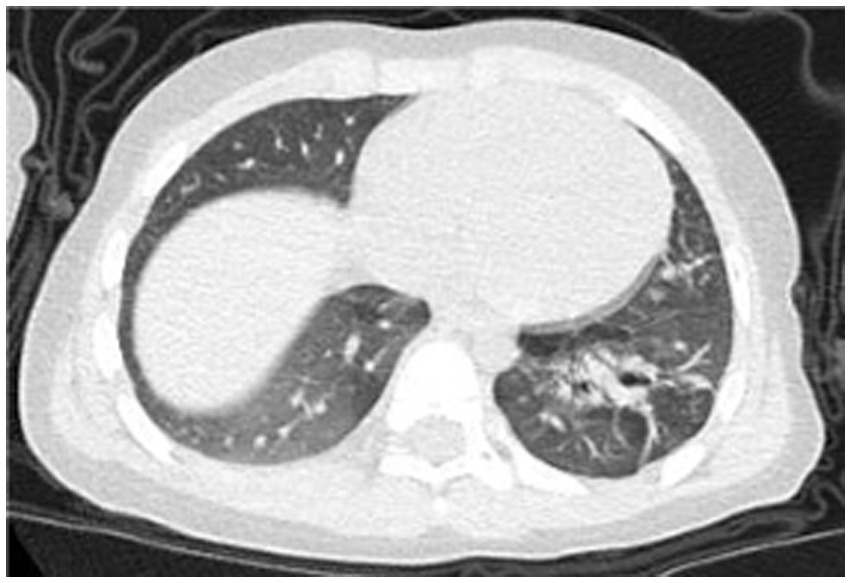

A 2-year-old male patient presented with a 7-day history of paroxysmal cough with sputum and rhinorrhea, followed by 4 days of fever (peak temperature 39.7 °C). No wheezing or shortness of breath was noted. Prior outpatient treatment with cefuroxime, azithromycin, and methylprednisolone sodium succinate yielded no improvement. Initial blood tests revealed white blood cell count (WBC) 3.7 × 10^9/L, lymphocytes (LY) 26%, neutrophils (NEUT) 67%, hemoglobin (HGB) 120 g/L, platelet count (PLT) 243 × 10^9/L, and C-reactive protein (CRP) 148.24 mg/L. Chest computed tomography (CT) (Figure 1) indicated pneumonia with lung consolidation, prompting hospital admission for severe pneumonia.

Figure 1

Chest CT scan on the 6th day of the illness.